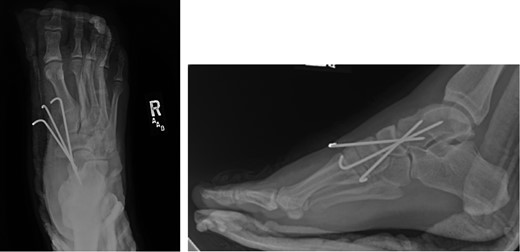

Once general anesthesia was induced, closed reduction was attempted using axial traction with the knee in flexion. Closed reduction was unsuccessful once again (Fig. 3) so the decision was made to attempt open reduction. An anteromedial approach was used dissect down to the talonavicular joint. Retractors were placed with care to avoid injury to tibialis anterior tendon or superficial peroneal nerve. The joint capsule was seen to be disrupted and further exposure revealed a thin, coronal fracture of the anteromedial aspect of the talar head measuring roughly 2 cm in length and 6 mm in thickness (Fig. 4). Once this fragment was removed, the subtalar and talonavicular joints were easily reduced. It was thought that this incarcerated fragment was the likely cause for the unsuccessful closed reduction. The talar head fragment was unamendable for stabilization due to its small size with poor healing potential, thus it was removed. The talonavicular joint was then percutaneously pinned in retrograde fashion with three K-wires (Fig. 5) to maintain anatomic reduction of the subtalar and talonavicular joints and the foot was splinted. At 2 weeks follow-up the patient was doing well and radiographs revealed no interval loss of reduction (Fig. 6).

Some studies suggest obtaining a CT scan of the ankle postreduction to check anatomic reduction as well as assess for other fractures [8, 9]. In our case, we did not obtain a postreduction CT scan. The subtalar and talonavicular joint were well visualized intraoperatively and were found to have no other associated fractures. In addition, anatomic reduction was obtained and under direct visualization and confirmed with fluoroscopy. Due to residual instability following reduction, K-wires were used to stabilize and hold the reduction. K-wire transfixation is supported in the literature for subtalar dislocations which tend to redislocate [10]. In other cases, where the joint is stable after reduction, there is no need for fixation.